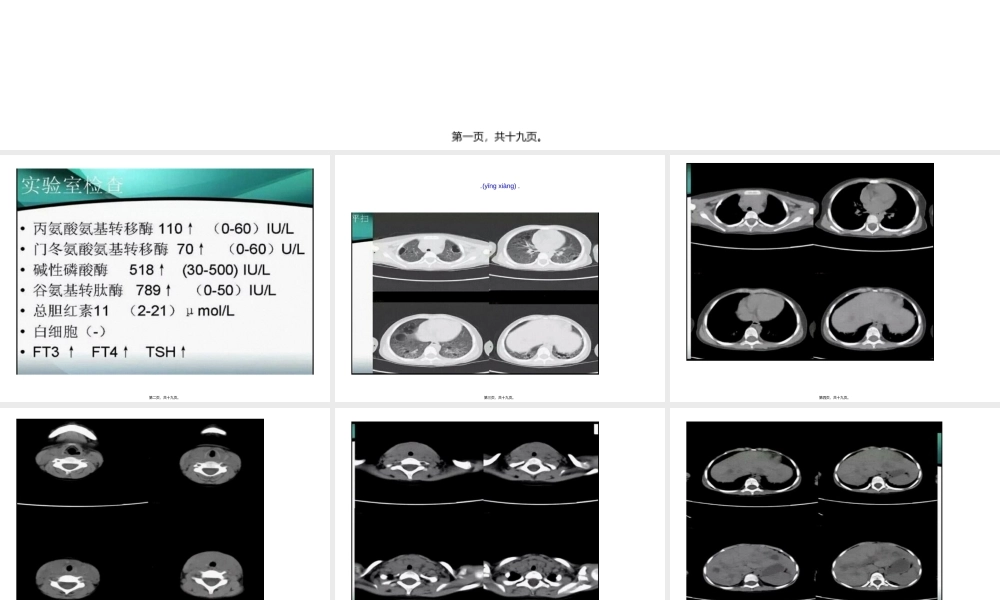

病例(bìnglì)分析第一页,共十九页。第二页,共十九页。影像(yǐnɡxiànɡ)表现第三页,共十九页。第四页,共十九页。第五页,共十九页。第六页,共十九页。第七页,共十九页。第八页,共十九页。第九页,共十九页。第十页,共十九页。第十一页,共十九页。第十二页,共十九页。第十三页,共十九页。第十四页,共十九页。第十五页,共十九页。第十六页,共十九页。第十七页,共十九页。病理:颈淋巴结活检病理:朗格罕斯细胞(xìbāo)组织细胞(xìbāo)增生症小结:朗格罕斯细胞(xìbāo)组织细胞(xìbāo)增生症(LCH)是一种少见的原因不明的肉芽肿性疾病,发病率约为0.5/10万~1/10万,可以是单一器官或多系统多器官受累,骨骼最为常见,其次为皮肤、中枢神经系统、肝胆和脾脏,肺、淋巴结、软组织、骨髓、腺体及胃肠道等。本病可发生于任何年龄,但50%以上病例发生于1~15岁儿童,发病高峰为1~4岁,男女之比约2:1。【影像学表现】1.骨骼:颅骨、股骨、脊柱及肋骨为常见发病部位,①活动期:表现为类圆形圆形或不规则形单囊或多囊状溶骨性破坏,患骨轻度膨胀,皮质可碎裂,形成软组织肿块,此期在病理上以嗜酸性粒细胞(xìbāo)及朗格罕氏组织细胞(xìbāo)增生为主。②修复期:表现为骨破坏减少,增生增多,长骨骨干可增粗,密度增高。2.肺部:早期病变在CT上以结节状表现为主,晚期则以囊疱状表现为主,结节直径多小于10mm,结节多位于两肺上叶,下叶基底段少见,囊疱为薄壁或厚壁,少部分相邻囊疱融合成不规则形,结节可以向囊疱转变,囊疱间肺组织轻度磨玻璃样密度增高。3.肝脏:朗格罕斯细胞(xìbāo)和炎性细胞(xìbāo)浸润引起门静脉周围炎症和水肿,表现为带状或结节状低密度影,增强后可见强化;易于侵犯胆管,致硬化性胆管炎,导致胆管扩张。4.中枢神经系统:①占位性病变:垂体和下丘脑是LCH最早最常见的中枢神经系统部位,临床上以中枢性尿崩症为首发症状,在MR上表现为垂体柄增粗,增强呈渐进性均匀强化,但病变也始于脑内任何一个部位的血管外膜,并逐渐形成肉芽肿样肿块。②变性性病变:可发生于小脑齿状核、基底节区及脑干对称性炎性病变。5.其他:发生于腺体及淋巴结,主要表现为体积增大;发生于肌肉等软组织在MR上表现为T1等或低信号,T2为高信号,增强扫描有较明显强化。第十八页,共十九页。内容(nèiróng)总结病例分析。病理:颈淋巴结活检病理:朗格罕斯细胞组织细胞增生症小结:朗格罕斯细胞组织细胞增生症(LC...